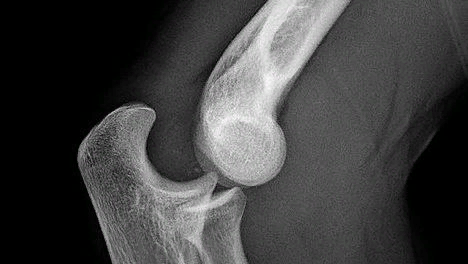

Вывих - смещение суставных концов костей, при котором утрачивается их правильное соприкосновение. Вывихи обуславливаются чрезмерным движением в суставе (при сильном ударе в область сустава, падении). Как правило, вывихи сопровождаются разрывом суставной сумки и разъединением сочленяющихся суставных поверхностей. Попытки сопоставить части безуспешны и сопровождаются сильнейшей болью и пружинящим сопротивлением. Вправление травматического вывиха должно быть как можно более ранним. Чаще всего вывихи бывают плечевого и локтевого суставов, большого пальца и тазобедренного сустава...